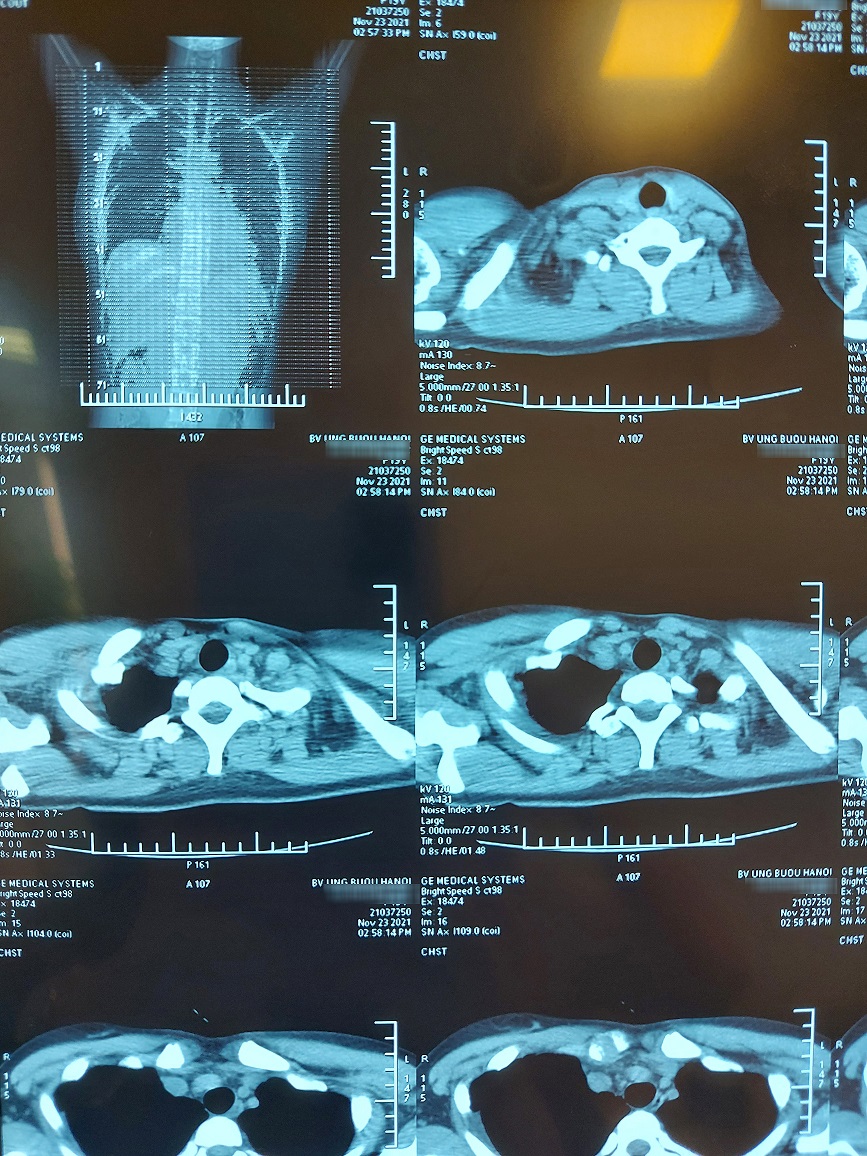

Phim chụp trước và sau phẫu thuật của bệnh nhân

TS.BS. Phan Lê Thắng – Trưởng khoa Ngoại Theo yêu cầu cho biết, vị trí u nằm ở trung thất trước trên bên phải, tổ chức u có cả lông, tóc, mỡ, xương. Khối u to, đè đẩy tim, chèn ép làm xẹp phổi, dính nhiều cơ quan nội tạng xung quanh.